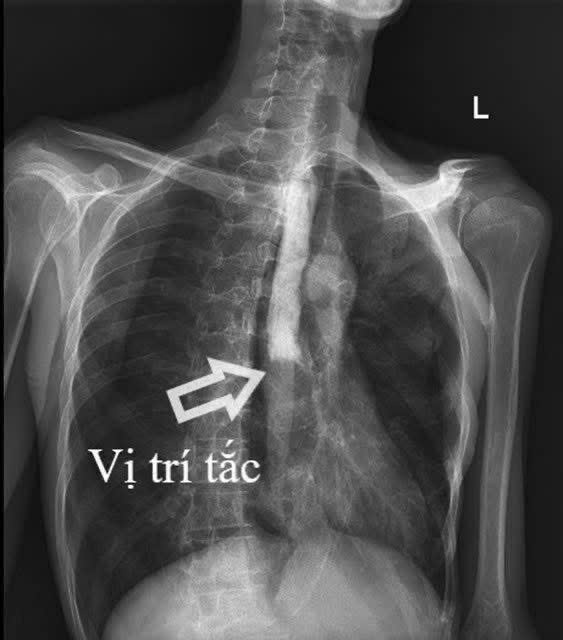

Hình ảnh vị trí bị tắc hoàn toàn thực quản đoạn 1/3 giữa.

Kết quả cận lâm sàng cho thấy bệnh nhân bị tắc hoàn toàn thực quản đoạn 1/3 giữa, kèm viêm lan tỏa dạ dày, ruột non và viêm phúc mạc. Tổn thương xuất hiện ở nhiều vị trí khiến việc xác định nguyên nhân trở nên đặc biệt khó khăn, với nhiều khả năng như lao, ung thư (lymphoma) hoặc bệnh lý tự miễn (Crohn).